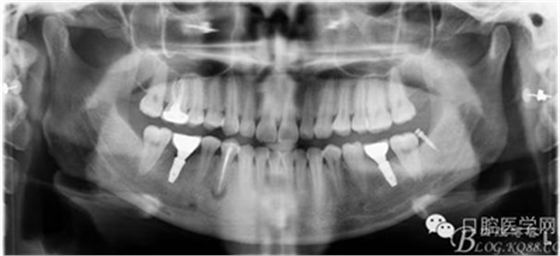

戴牙后忘記拍口內(nèi)照片了,只有一張X片,下次復(fù)診在補(bǔ)拍 44患者不愿冠修復(fù)

去除了支抗釘,要求患者3個(gè)月復(fù)查。